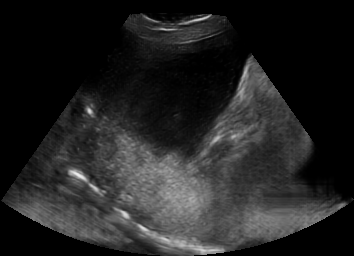

Real in-vivo images. 22 ultrasound sequences were collected using a GE Voluson E8 machine during standard fetal screening exams of 8 patients. Each sequence is several seconds long. We extracted all 4427 frames and resize them to , see Fig. 2 for some examples. The resulting image set was randomly split into training-validation-test sets by a 80-10-10% ratio.